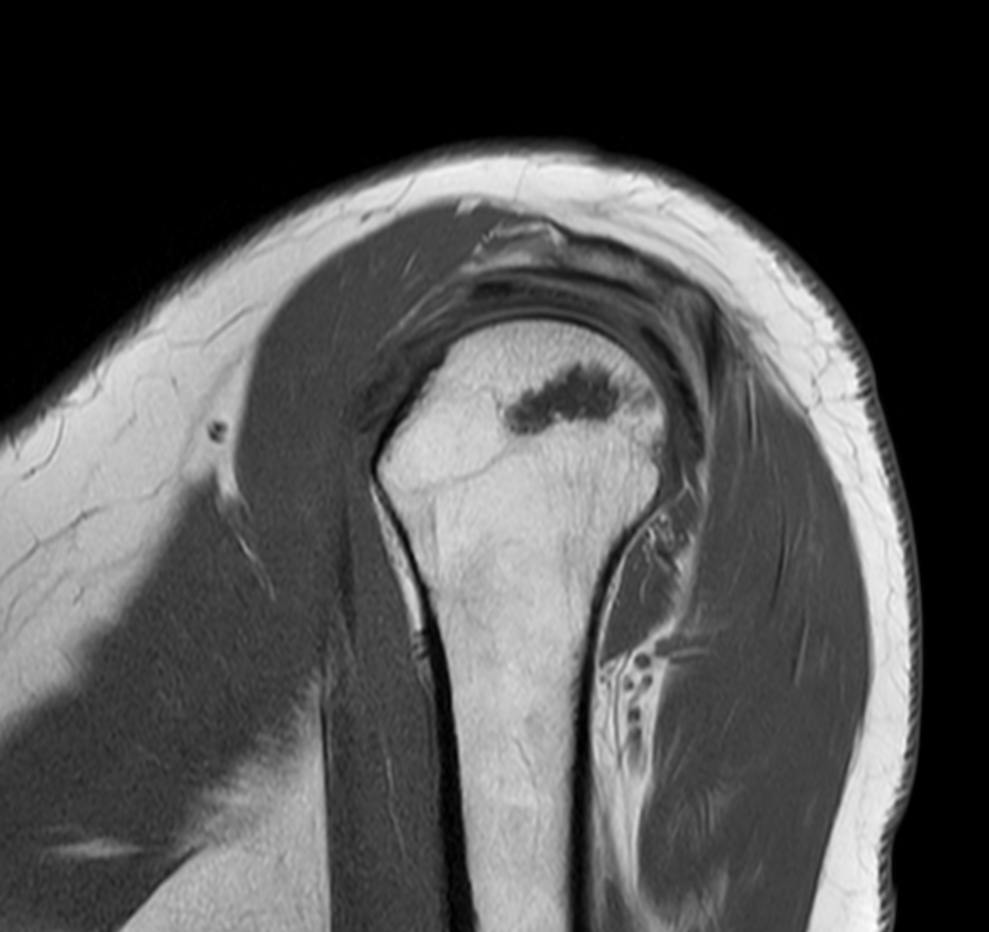

Coronal T1w TSE

Coronal T1w SPIR